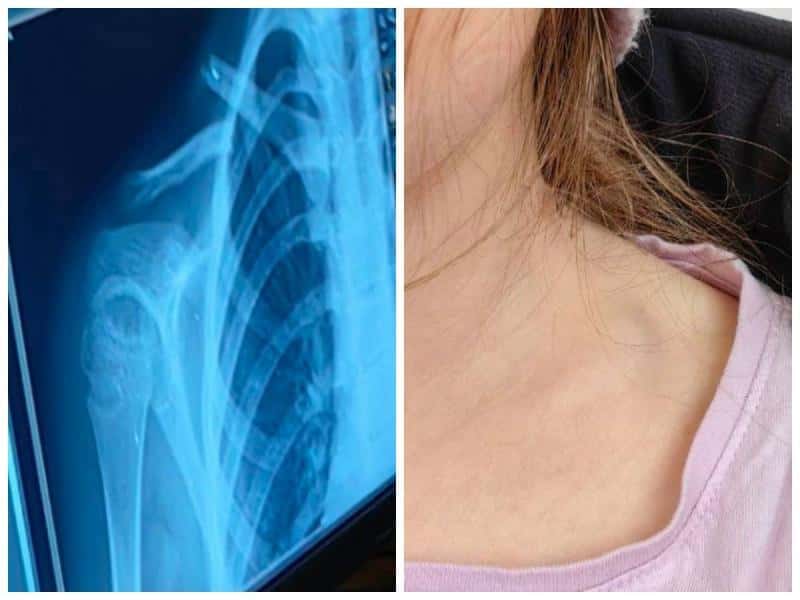

Фото: юрист Юлия МайороваВ Каменске-Уральском школьница получила травму в одной из городских игровых комнат — девочка праздновала там день рождения и во время прыжков на батуте упала, сломав ключицу. На место происшествия вызвали скорую помощь. Ребенка доставили в больницу, где она проходила лечение.

По словам юриста Юлии, девочка уже идет на поправку, травма заживает, и она возвращается к привычной жизни.